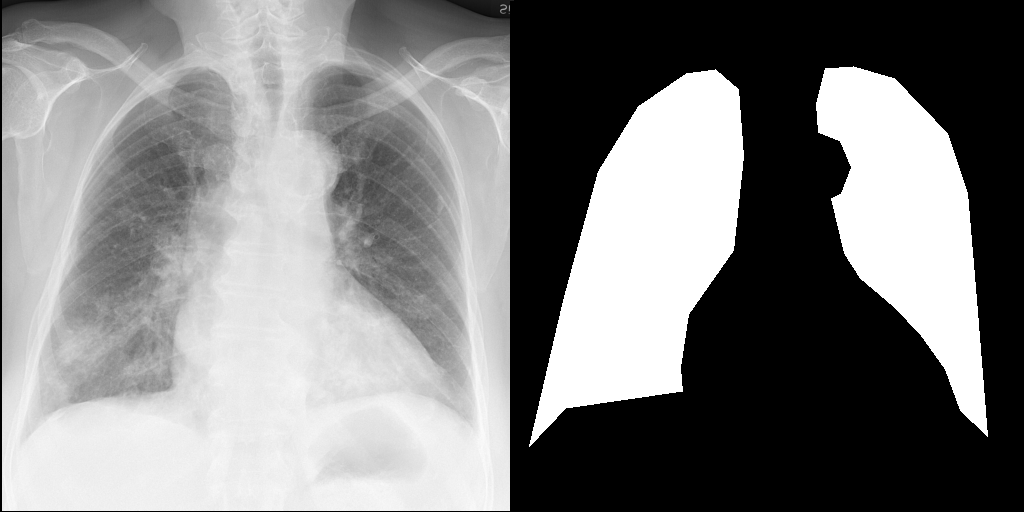

Let's load an example image of a patient with influenza.

import requests

input_image = transforms.Compose([transforms.Resize(512), transforms.CenterCrop(512)])(image)

right_lung_coords = [(19, 445), (53, 299), (88, 170), (128, 105), (176, 72), (205, 68), (228, 88), (233, 155), (223, 249), (178, 313), (170, 366), (172, 390), (55, 407)]

left_lung_coords = [(477, 435), (466, 298), (457, 192), (437, 132), (384, 77), (343, 65), (315, 67), (306, 102), (308, 131), (330, 140), (341, 166), (331, 192), (321, 197), (334, 252), (350, 277), (383, 305), (410, 333), (435, 368), (450, 409)]

# Create a blank image with the same size as the original image

lung_mask = Image.new("L", (512, 512), 0)

# Draw the filled shape using the coordinates

draw = ImageDraw.Draw(lung_mask)

draw.polygon(right_lung_coords, fill=255)

draw.polygon(left_lung_coords, fill=255)

For this example, we will remove the visual appearance of influence from the lungs, while preventing changes from happening to the rest of the image. To do this, we create a mask of the lung regions and use this as the edit_mask which defines the region we wish the editing prompt to be applied to. Since we want the rest of the image to remain unchanged, we use the inverse as the keep_mask which defines the region where edits are discouraged from taking place.

from PIL import ImageOps

edit_mask = lung_mask

keep_mask = ImageOps.invert(lung_mask)